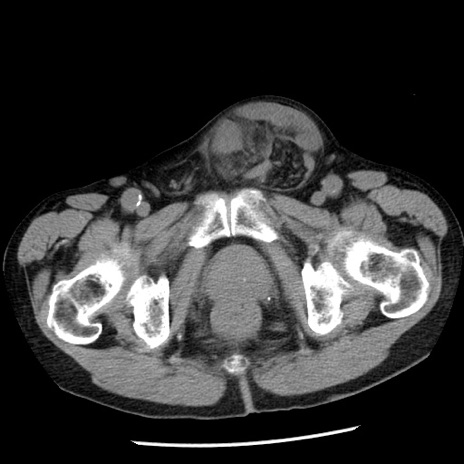

症例26(横断像)

【症例】80歳代男性

【主訴】嘔吐

【現病歴】昨晩2回嘔吐あり、今朝になっても嘔吐あり。来院。

【既往歴】胃潰瘍

【身体所見】意識清明、BT 37.6℃、BP 166/95mmHg、HR 100bpm、SpO2 97%、腹部:平坦・軟、腸蠕動音聴取良好、圧痛なし。

【データ】WBC 21900、CRP 1.46